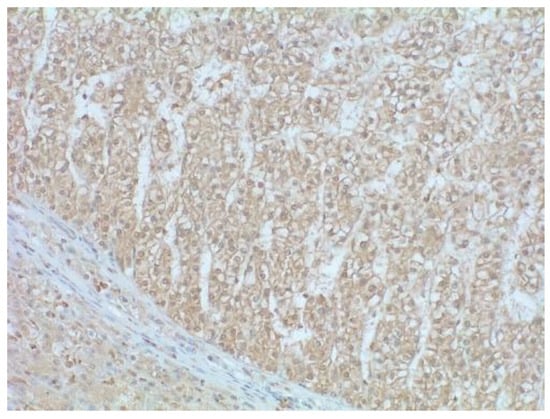

2.3. Immunohistochemistry

- Miskad, U.A.; Yano, Y.; Nakaji, M.; Kishi, S.; Itoh, H.; Kim, S.R.; Ku, Y.; Kuroda, Y.; Hayashi, Y. Histological study of PIVKA-II expression in hepatocellular carcinoma and adenomatous hyperplasia. Pathol. Int. 2001, 51, 916–922. [Google Scholar] [CrossRef] [PubMed]

- Tamano, M.; Sugaya, H.; Oguma, M.; Murohisa, T.; Tomita, Y.; Matsumura, A.; Kojima, K.; Terano, A. Immunolocalisation of PIVKA-II in paraffin-embedded specimens of hepatocellular carcinoma. Liver 1999, 19, 406–410. [Google Scholar] [CrossRef]

- Ajisaka, H.; Shimizu, K.; Miwa, K. Immunohistochemical study of protein induced by vitamin K absence or antagonist II in hepatocellular carcinoma. J. Surg. Oncol. 2003, 84, 89–93. [Google Scholar] [CrossRef]